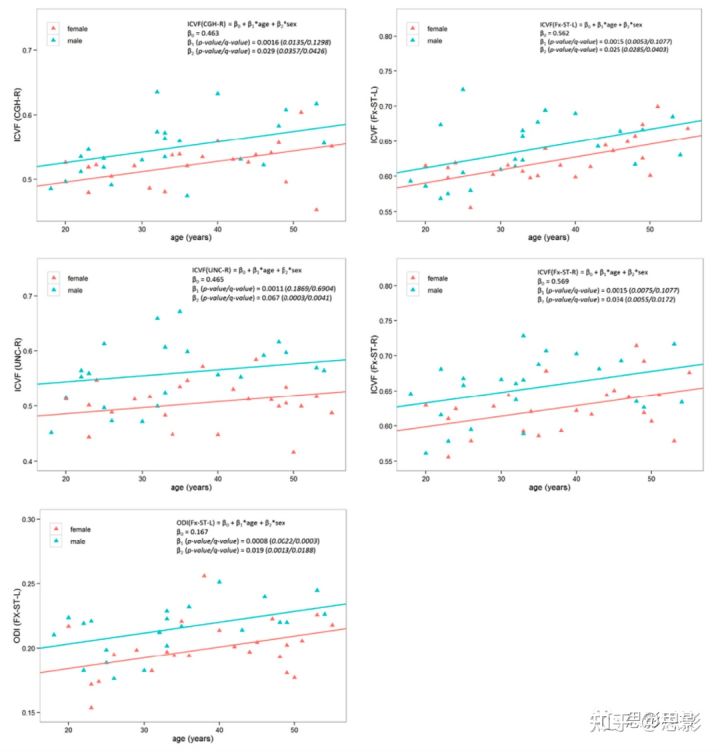

回归模型2的β2显著(Eq.8),则表明存在显著的性别差异。一些ROIs上有显著的性别差异,并且大多数显著性出现在NODDI模型的扩散指标中:ODI和ICVF(表2)。年龄相关的关键ROI中ICVF和ODI的回归线绘制在图3中,以显示在年龄纵向变化中的性别差异。男性大脑的ODI在左侧穹窿终末纹状体和右侧放射上冠处明显增大约7%(ODI绝对值约为0.017)。在13个ROI中,男性的ICVF显着高于7%,包括易受年龄影响的解剖结构(即扣带回的右前段、扣带回的右海马段、双侧穹窿-终纹和右侧钩状束)。7%的ICVF对应于0.04的绝对差异。DTI和P0在回归模型的斜率中没有显示出显著的性别差异。

图3 模型2中女性(红色)和男性(蓝色)的线性回归结果。

β1表示男女相同的衰老速率。β2表示女性和男性回归线之间的纵向偏移量(即截距)。p值表示未校正的显著性水平,q值表示48个ROI的多重比较的错误发现率(false discovery rate,FDR)。注意,以q<0.05为显著性标准,此处显示,除了ODI以外,大多数β1与原假设没有显著差异,即β1 = 0;但是β2在女性和男性之间存在显著差异。